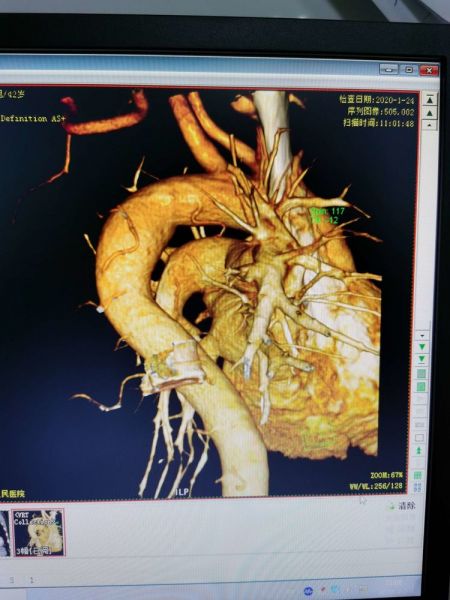

我院CTA发现两只粗大支气管动脉。